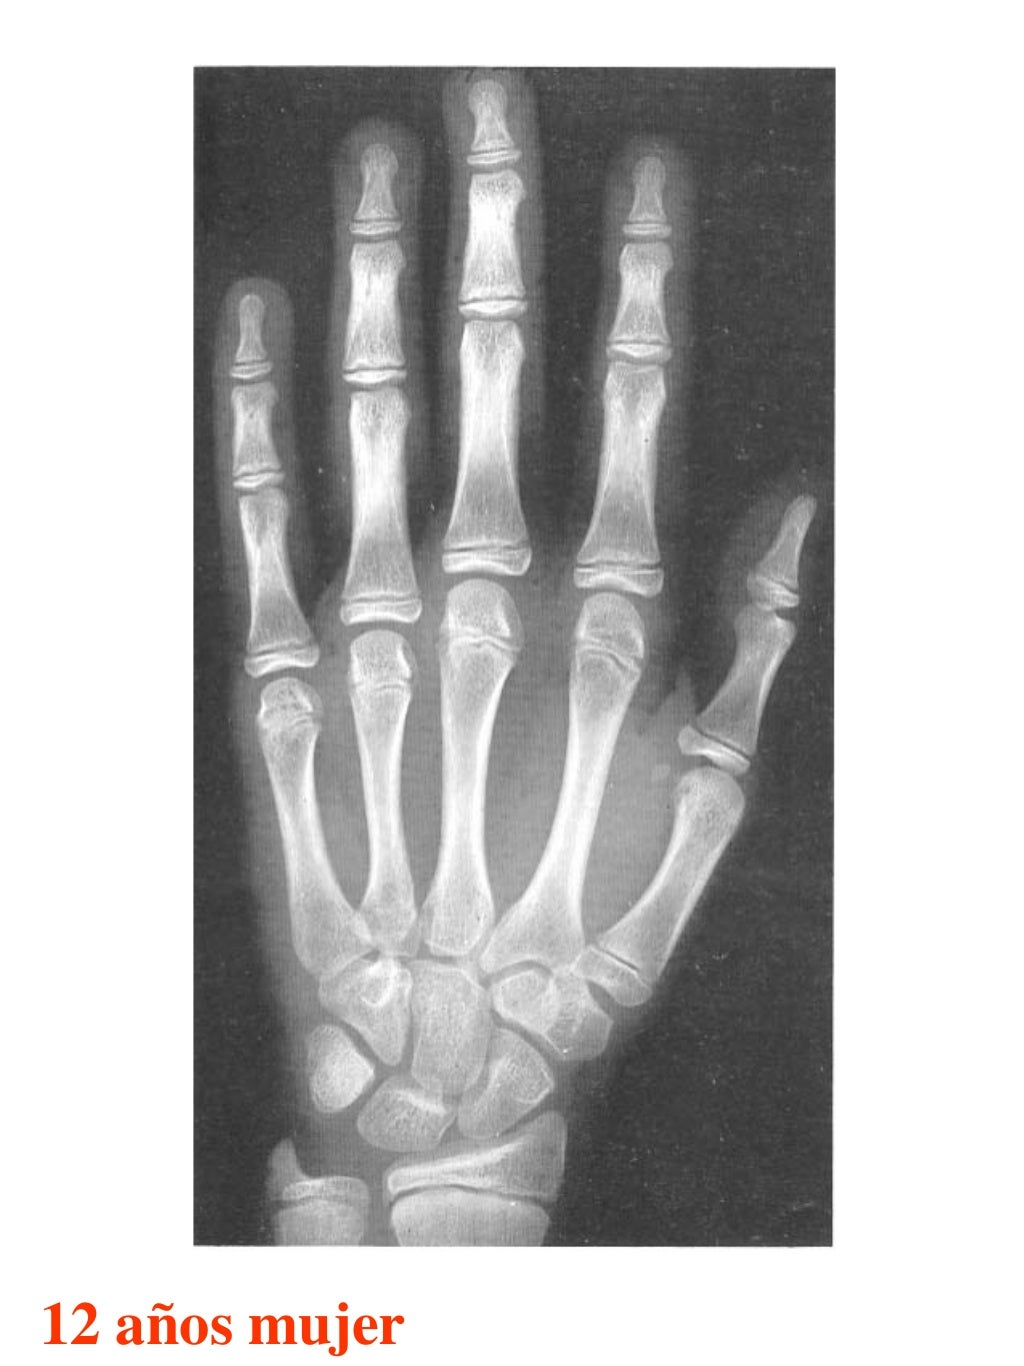

Tablas De Greulich Y Pyle The standards established by greulich and pyle, undoubtedly the most popular method, consist of two series of standard plates. The standards established by greulich and pyle, undoubtedly the most popular method, consist of two series of standard plates. El documento lista las edades. This systematic review summarizes the. The greulich and pyle method is one of the two main ways to assess the bone age of children. Both main methods of bone age. Scribd is the world's largest social reading and publishing site. 153 recomendaciones • 616,869 vistas. Atlas greulich y pyle | pdf | descarga gratuita. The greulich and pyle atlas is used to estimate the age of children and adolescents. The radiographic atlas of skeletal development of the hand and wrist by ww greulich and si pyle is a classic radiological.

Atlas greulich y pyle Tablas De Greulich Y Pyle The standards established by greulich and pyle, undoubtedly the most popular method, consist of two series of standard plates. Atlas greulich y pyle | pdf | descarga gratuita. Scribd is the world's largest social reading and publishing site. 153 recomendaciones • 616,869 vistas. The radiographic atlas of skeletal development of the hand and wrist by ww greulich and si pyle. Tablas De Greulich Y Pyle.

Atlas greulich y pyle Tablas De Greulich Y Pyle Both main methods of bone age. 153 recomendaciones • 616,869 vistas. The greulich and pyle method is one of the two main ways to assess the bone age of children. The standards established by greulich and pyle, undoubtedly the most popular method, consist of two series of standard plates. Scribd is the world's largest social reading and publishing site. This. Tablas De Greulich Y Pyle.